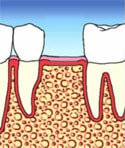

Nach einer Einheilphase von normalerweise 3 bis 6 Monaten legt der Zahnarzt in einem kleinen Eingriff die Implantatköpfe frei. Nach der Freilegung nimmt er dann einen Abdruck und fertigt die prothetische Versorgung der Implantate im zahntechnischen Labor an.